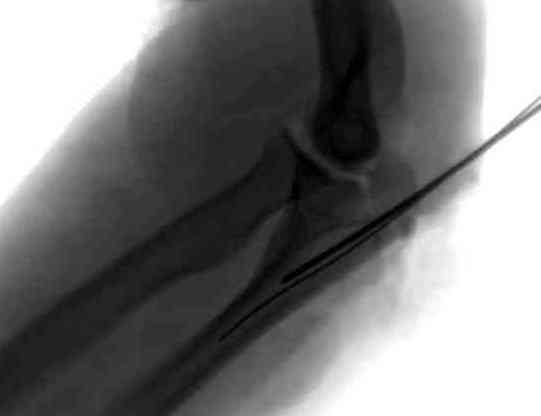

Здесь выставлены несколько случаев и варианты фиксации локтевого

отростка, некоторые в комбинации с другими переломами.

Имя     : 1 olecranon injury lat 2.jpg

Тип     : image/jpeg

Размер  : 16317 байтов

Описание: отсутствует

Url     : http://weborto.net:8080/pipermail/ortho/attachments/20071121/9a993135/attachment-0006.jpg